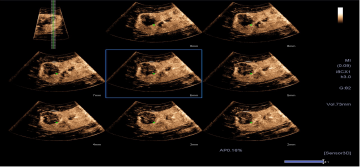

4D造影谐波成像技术(4D CHI):

1. 可应用于妇科领域,包括4D子宫输卵管造影;

2. 具备多切面显示功能,像观察CT片一样,更为全面了解病变的灌注情况。

造影定量分析(CHI-Q):

1. 可提供精确的造影剂灌注的定量分析数据用于临床诊断与科研。

2. 自动的ROI 追踪技术可有效消除呼吸运动的影响,提高定量精度。

3. 造影成像原始数据存储可以方便实现在机和脱机的定量分析